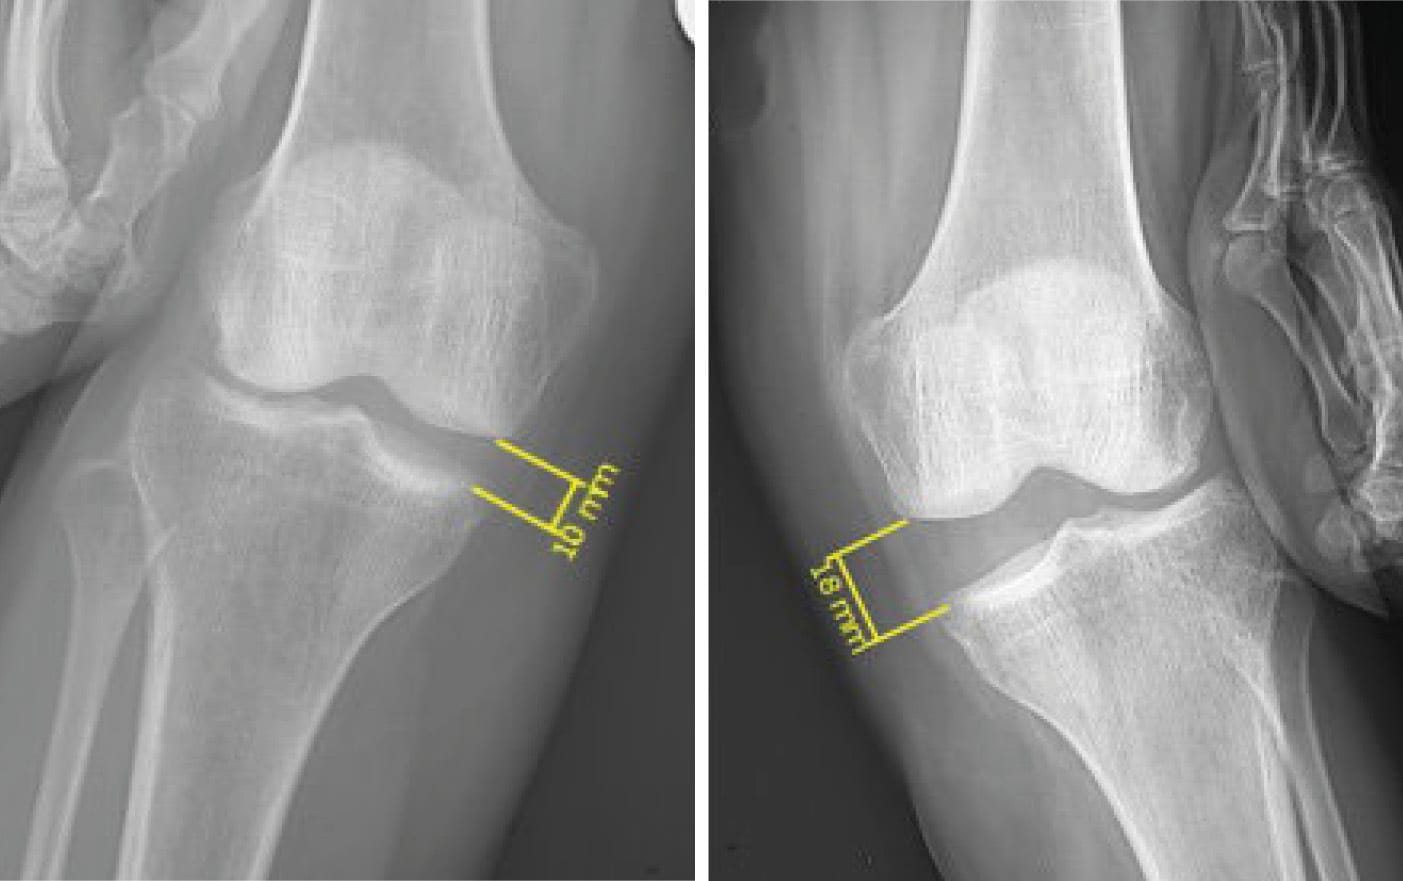

• Radiography: Weight-bearing plain film radiographs (AP, lateral and femoropatellar) are the first investigations to perform. In the acute phase, these are able to detect associated bone injuries (fractures, avulsions) (figure 6) and any soft tissue swelling.

In the chronic phase, stress radiographs are also used to measure opening of the joint space under valgus forces (figure 7). Bilateral radiographs must be taken for comparison. An increase exceeding 3 mm in 30° of flexion demonstrates a complete tear of the sMCL, an increase of around 10 mm indicates an sMCL and dMCL injury and exceeding 10 mm is a combined MCL and POL injury, often in conjunction with an injury to one or both cruciate ligaments [8] Laprade RF, Bernhardson AS, Griffith CJ, Macalena JA, Wijdicks CA. Correlation of valgus stress radiographs with medial knee ligament injuries: an in vitro biomechanical study. Am J Sports Med. févr 2010;38(2):330-8. .